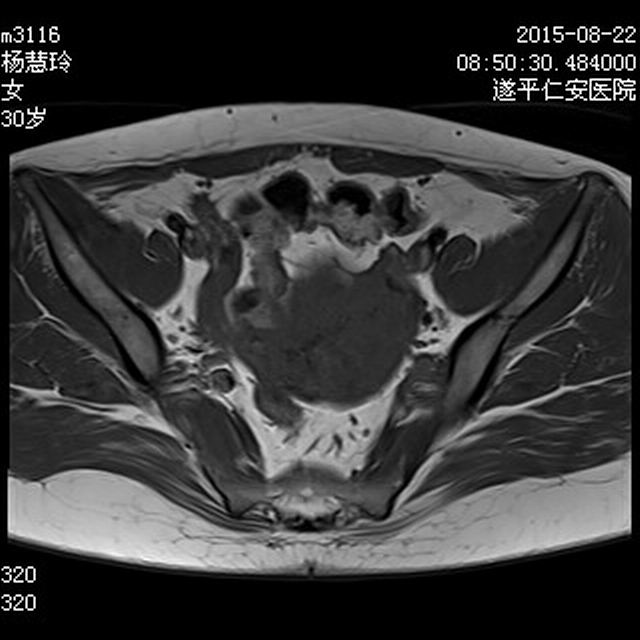

MRI6753:盆腔MRI

【结果公布】 女,30岁,不规则阴道流血一月余,HCG在正常范围。半年前曾做过人流,之后月经量少。

病理结果为子宫疤痕处妊娠。

最近翻看图像时看到这个病例,记得有病理的,终于在U盘中找到。病理结果为子宫疤痕处妊娠。上图扫描序列按顺序应为TIWI T2WI DWI T2WI矢状位 矢状位增强图像。